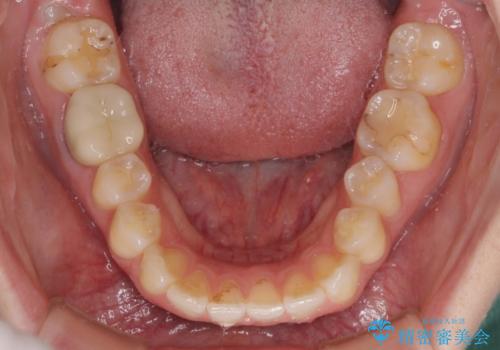

- 矯正治療の後戻りが気になるとのことで来院された患者様です。

上顎の後戻りをインビザライン・ライトで治療することとしました。

上顎のみの治療を希望されたため、咬み合わせをしっかりと改善することはできませんでしたが、審美面が大きく改善され、日常生活の機能面でも不具合を感じることはなく、大変満足していただきました。